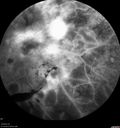

71 year old female - About 1 year ago the patient had injections in each eye and also started with laser. Hurricane Irma hit and she had her appointments cancelled and she did not go back. She had cataract surgery previously but no other treatment. About a month ago she noticed that her vision was declining in the left eye and then a few weeks ago it got a lot worse. The right eye is pretty good and she can see with her reading glasses. She is planning to get bifocals in the future. She did not want to get new glasses until we figured out the left eye. VA OD: sc20/25-2 VA OS: sc1’/200 IOP: TP: OD:15 OS:15 The left eye has no macular edema or macular detachment and an APD. The vision loss is likely from a CRAO or from optic atrophy. So a PPV was not done.

Severe PDR with preretinal fibrosis435 views71 year old female untreated for a year following injections because of hurricane Irma. VA 20/30 OD and 5/200 OS. Sudden vision loss 1 month ago left eye was likely an ischemic event. Right eye is being treated with injections and PRP laser.00000